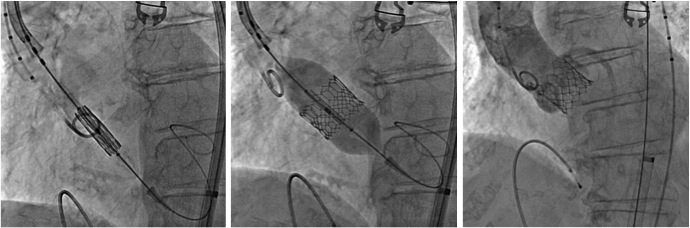

ICPS(写真1)という施設はパリ郊外のMassyという所にあるcardiology、特にinterventionがメインの病院で、年間1万件ほどのCAGおよび2000件前後のPCIを施行しているhigh volume centerです。またcoronary interventionだけでなく、TAVI、MitraClip、LAA閉鎖術(写真2)といったstructural heart disease (SHD)に対するinterventionもさかんに行われております。特にaortic stenosis (AS) に対するTAVIに関しては、週5〜6件、年間200件以上の症例を施行しており、Edwards SapienXTやCoreValveといった第1世代でバイスだけでなく、Edwards Sapien3(写真3)やLotus valveといった第2世代デバイスも積極的に使用している施設です。

Arai1-3

写真3